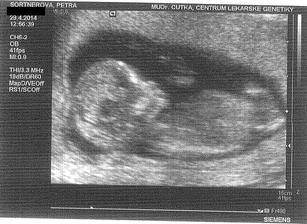

* 29.4.2014 objednané vyšetření v Centru lékařské genetiky - UZ na vývojové vady, tak snad to dopadne dobře - Tak dnešní screening dopadl na 1*... Všechno naprosto dokonalé, miminko zdravé, testy i UZ v pořádku. Mimčo měří 6 cm. Bylo krásně natočené a mávalo nám ručičkama. Paní doktorka nám vše krásně vysvětlila a ukázala... Manžel byl nadšený a je pyšný, protože budeme mít na 80% holčičku 🙂 Jsme nesmírně šťastní 🙂